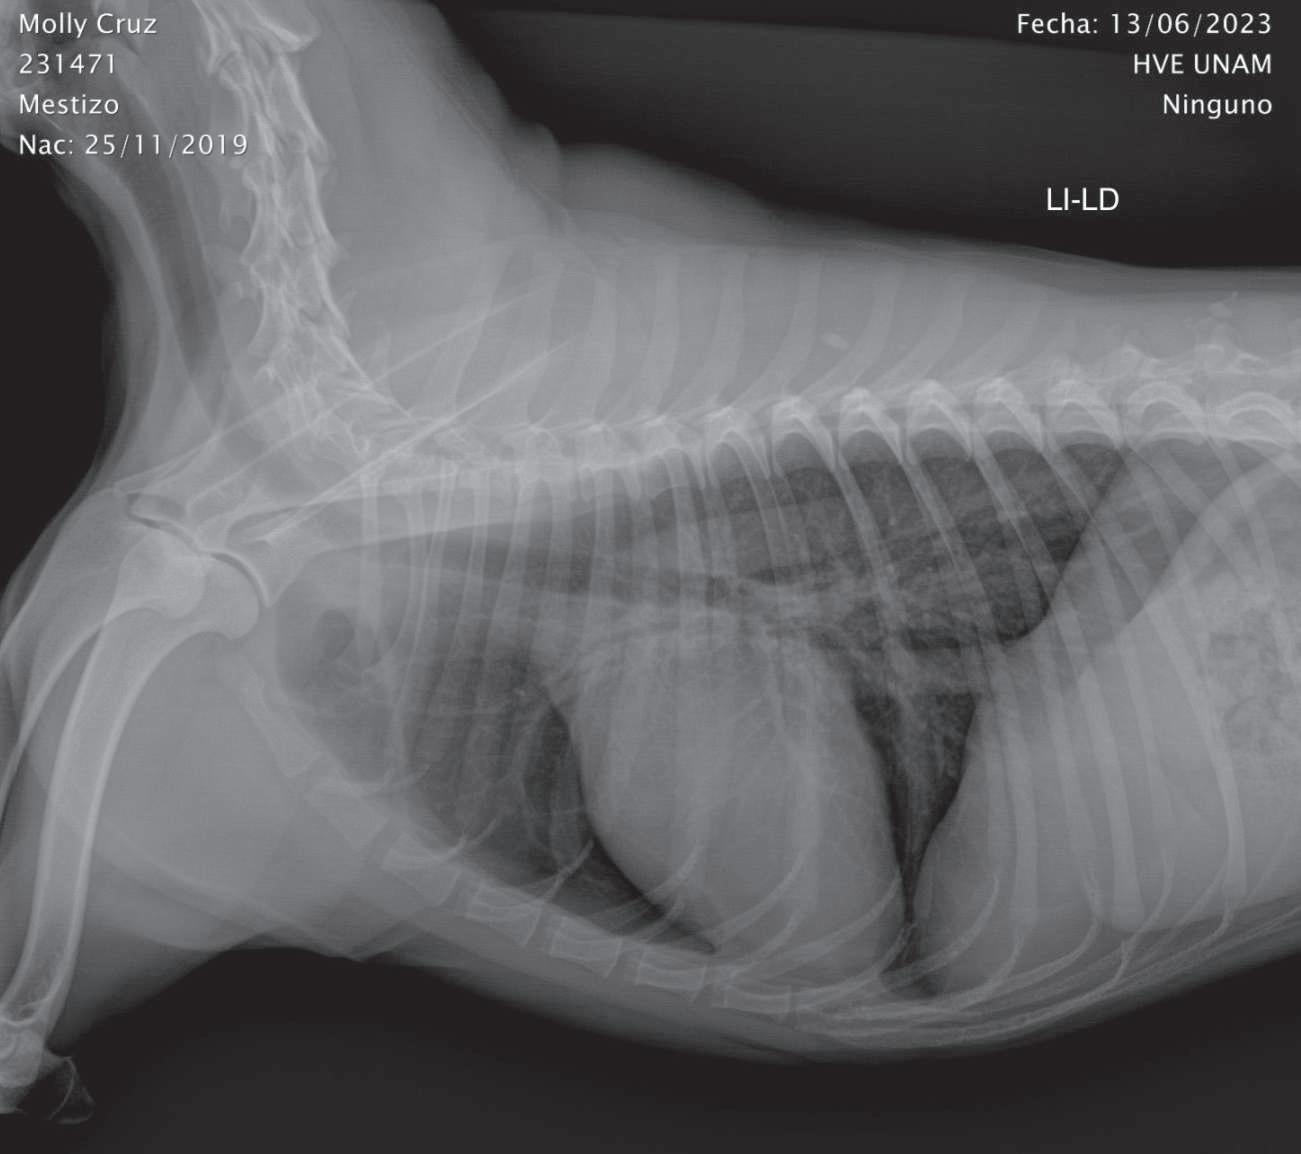

Estudio radiográfico con medio de contraste positivo (sulfato de bario), Li- Ld. Se observa que el medio de contraste pasó en su totalidad al estómago. (p.

Alrealizarexamenfísicogeneral,noes evidenteningunaanormalidad.Portalmo-

tivo, en un intento de diferenciar vómito de regurgitación, se realiza estudio radiográficosimple(sincambiosradiográficos aparentes) (Figuras 1 y 2) yconmediode contraste (sulfato de bario) (Figura 3); se encuentra un tránsito normal del esófago y del estómago.